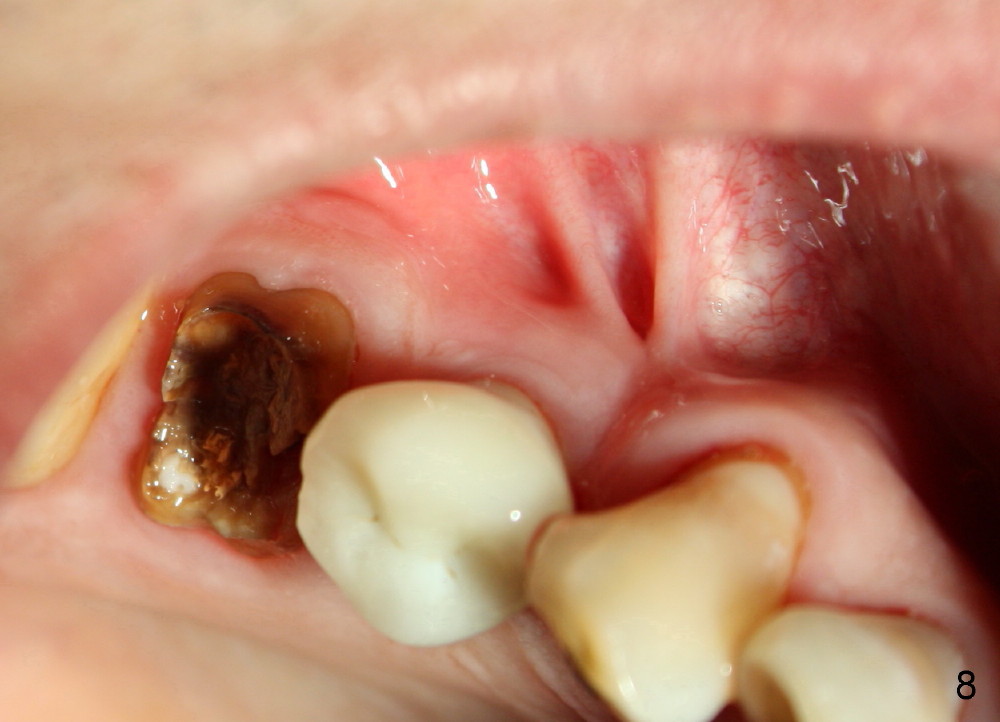

Eleven months post cementation, the patient returns for #3 crown recementation. The buccal plate atrophy over the implant is minimal (Fig.8).